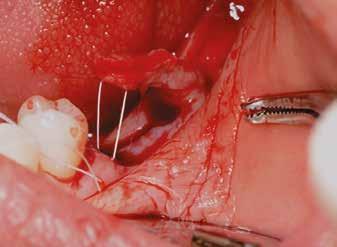

Egy 47 éves páciens jelentkezett nálunk egy alsó, hátsó foghiánnyal, ahol jelentős csontfelszívódást tapasztaltunk a moláris fogak korábbi eltávolítása miatt (1. ábra). Két implantátum körül is volt ínyrecesszió, illetve a keratinizált íny mennyisége minimális volt (kevesebb, mint 1 mm). 4 hónappal az implantációt követően ínykorrekciót végeztünk.

Sebészi technika

Helyi érzéstelenítést végeztünk a műtéti területen artikain és 1:100 000 adrenalin segítségével. A recipiens területet előkészítettük, élesen disszekciót végeztünk, hogy egy izomtapadástól mentes periosteum ágyat képezhessünk. Ettől disztálisan két párhuzamos parakresztális metszést végeztünk egy 15C-s szikepengével, majd a metszéseket egy

horizontális metszéssel kötöttük össze (2–5. ábra). A metszések hosszát és a köztük lévő távolságot minden esetben a lágyszövet augmentációhoz szükséges keratinizált szövet határozza meg. A lebeny deepitelizációját egy 15C-s szikepengével végeztük (6. ábra). Ezt követően félvastag lebenyt preparáltunk (7. ábra). A lebenyt apikálisan, az alapjáról belső, felületes metszéssel felszabadítottuk, hogy passzívan áthelyezhessük és rögzíthessük, feszülés nélkül. Meziális irányba 180 fokkal átforgattuk (8–9. ábra). A meziális papillát alagúttechnikával (tunnelling technique) készítettük elő a graft befogadására (10. ábra). Az így kialakított lebenyt a recipiens ágyban rögzítettük az újonnan kialakított vesztibulum alapjánál 5-0 nem felszívódó PTFE (Coreflon, IMPLACORE) varratokkal. A graftot behajtottuk az ínyszél alá és meziális oldalon rögzítettük PTFE varratokkal (11–14. ábra)

A műtétet követően napi kétszeri, 0,12%-os klórhexidin tartalmú szájvízzel történő öblögetést javasoltunk a páciensnek, két héten keresztül. Gyulladáscsökkentésre 8 óránként 400 mg Ibuprofént javasoltunk, három napon keresztül. A páciens elmondása szerint sem fájdalmat, sem különösebb diszkomfortot nem tapasztalt. Ezt követően, további 4 héten keresztül, 0,2%-os klórhexidin tartalmú szájvízzel történő öblögetést javasoltunk a betegnek és instruáltuk, hogy lehetőleg ne mossa fogkefével az érintett területet. A varratokat egy héttel később távolítottuk el. A donor és a recipiens terület – 10 nappal a műtétet követően – kiválóan gyógyult (15–16. ábra). Az ezt követő kontrollokat a következő időpontokban ejtettük meg: kettő, illetve négy héttel a műtét után, majd három, hat és tizenkét hónappal később, ezt követően pedig félévente (17–20. ábra). Minden kontroll alkalmával professzionális fenntartó kezelést végeztünk a területen.